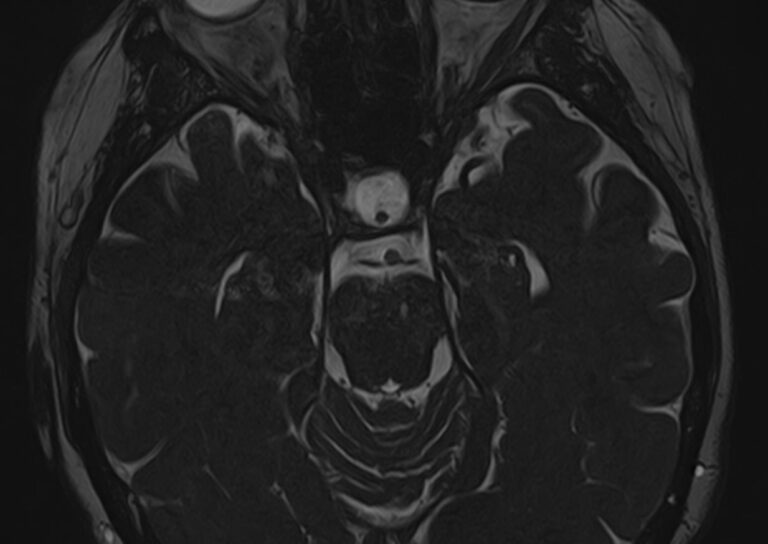

Магнитно-резонансная томография позволяет детально визуализировать изменения черепных нервов и прилегающих структур. В клинике «Доступная медицина» для точной диагностики причин поражения черепно-мозговых нервов применяется новейший высокопольный 32-канальный томограф TOSHIBA VANTAGE TITAN 1,5 Тесла, который обладает высокой чувствительностью и способностью определить минимальные изменения исследуемого органа.

Признаки нарушения функций ЧМН разнообразны. Причинами поражения могут быть серьезные заболевания, которые требуют незамедлительного обращения к врачу. Для установления точного диагноза в комплексе с другими методами используют МРТ и КТ головного мозга. Оба исследования имеют свои особенности. Компьютерная томография позволяет хорошо визуализировать изменения костной ткани. На МР-изображениях лучше просматриваются мягкотканные структуры, поэтому МРТ головного мозга с прицельным осмотром черепно-мозговых нервов является методом выбора в подобных случаях.